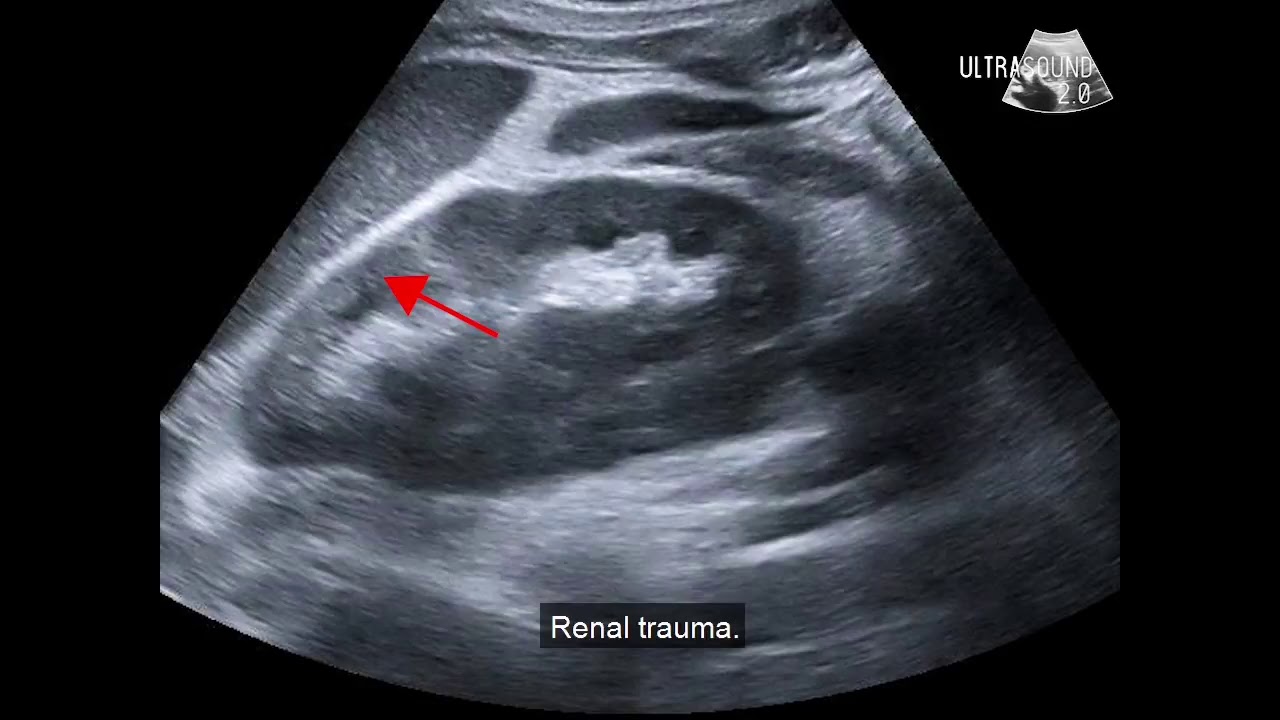

Introduzione I traumi addominali costituiscono il 30% delle lesioni osservate in traumatologia 1Sono associati a un’alta mortalità, nell’ordine del 10%, non solo a causa della gravità delle lesioni addominali, ma anche per altre lesioni comunemente associate nei pazienti politraumatizzati 2L’esistenza di uno shock emorragico aumenta in modo significativo la mortalità, che. A bordo di uno schizofrenico 1 stataleeditrice 2 Avantgarden Fernando Utano A bordo di Uno schizofrenico ISBN copyright 10, Statale 11 editrice wwwstatale11it soluzioni grafiche e realizzazione IceDream. In rare cases, the patients have fluid accumulation limited to the paracolic recesses which may be caused by isolated gastrointestinal injury In 30–40 % of women of childbearing age, a fluid collection of more than 50 ml in the pouch of Douglas is physiological In FAST, any amount of free fluid is generally considered a sign of internal injury.